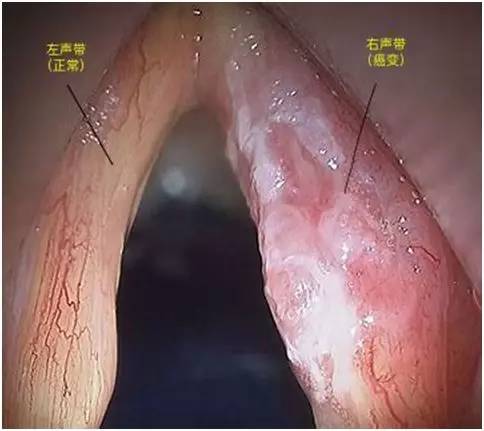

首先需要在喉镜下观察病变的外观。

图中所示的左声带,表面黏膜光滑,而右声带则变得粗糙,呈“菜花样”改变,这是绝大多数喉鳞癌的典型外观。

当看到这样的病变,就需要进行活检了。医生会直接钳取一小块病变组织进行病理检查明确诊断。